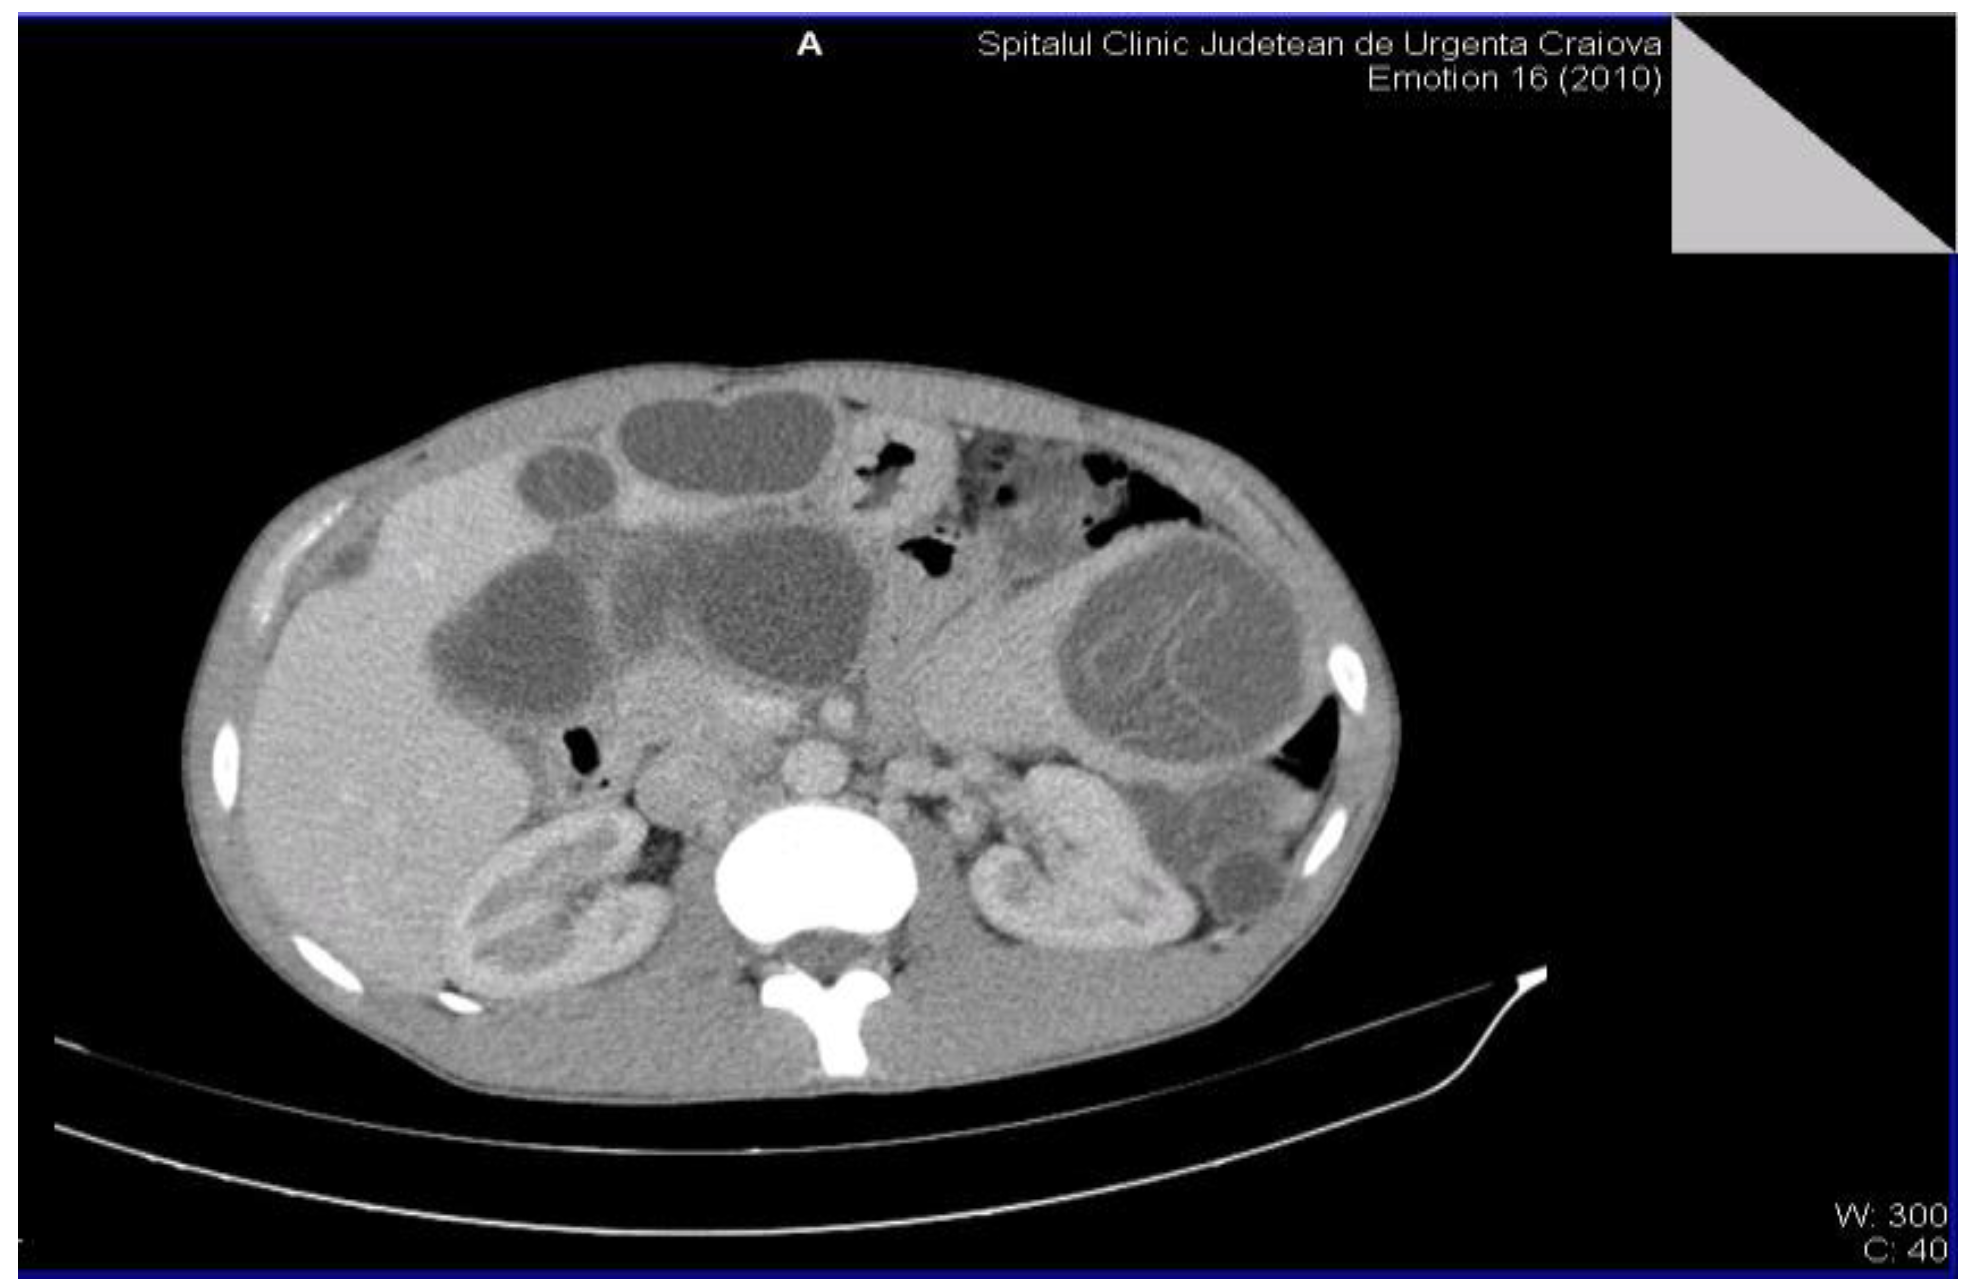

The definitive diagnosis of the retroperitoneal hydatid cyst was based on the anamnesis, clinical examination and paraclinical examinations, including serological examinations. The medical history of the patients was insignificant, but most of them were from rural areas and confirmed the close interaction with animals (sheep, goats, dogs). The clinical examination very rarely raises the suspicion of retroperitoneal hydatid cyst, the examinations of other systems and organs being normal. Most of the biological investigations were within normal limits. The serological examination by detecting the immunoglobulin G antibody by the ELISA method (enzyme-linked immunosorbent assay) was positive in all cases, showing high sensitivity and specificity and was only performed after raising the suspicion of hydatid cyst by imaging methods. Non-invasive imaging paraclinical investigations for the diagnosis of the disease were: abdominal (or regional) ultrasound, CT scan (computed tomography) and MRI (magnetic resonance imaging) that proved a high sensitivity. The presence of daughter cysts, hydatid sands, and floating membrane can confirm the diagnosis of hydatid cyst [6,7]. Abdominal ultrasound established the diagnosis in the case of 4 patients, and in the case of two patients it raised the suspicion of retroperitoneal hydatid cyst. The CT examination was carried out in 5 patients, for diagnostic purposes or for the remote evaluation of the lesions. In 2 patients, the tomographic diagnosis was accidental, without clinical or paraclinical suspicion of abdominal hydatid cysts and revealed their single or multiple presence, either only retroperitoneally or also intraperitoneally (Figure 2 and Figure 3).

Figure 2.

Multiple intra-abdominal hydatid cysts.

Figure 3.

Intra-abdominal hydatid cysts.